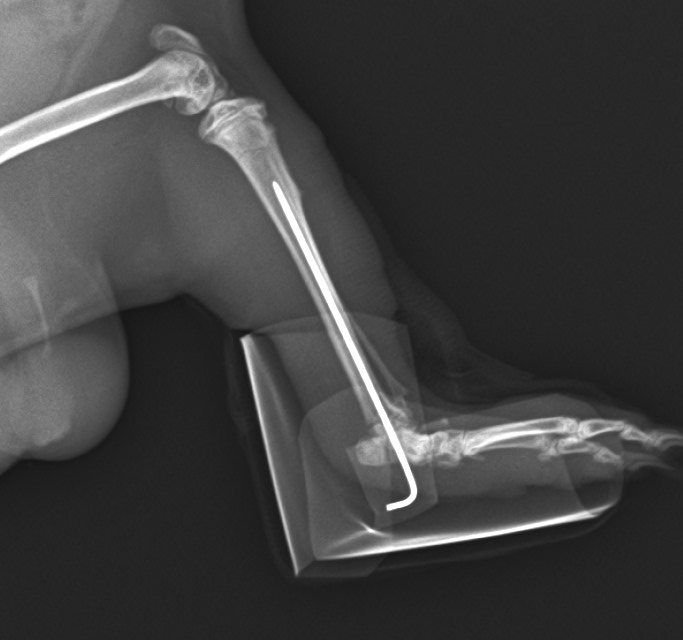

モルモットが後肢をかばっている(後肢:脛骨の骨折) 公開済み: 2024年11月12日更新: 2025年11月2日作成者: koizumi-nest モルモットの骨折は、特に後肢の脛骨(すねの部分)においてよく発生します。 特に若いモルちゃんによく見られるように感じられます。 骨折の仕方によって、手術による整復と固定を実施する必要があります。 モルモットの脛骨の骨折レントゲン写真。 踵関節の近くで骨折しています。整復・固定手術を行いました。 手術し、ギプス固定した後のレントゲン写真。 固定を外した後のレントゲン写真。 良好に骨癒合しており、これで治療は終了となりました。